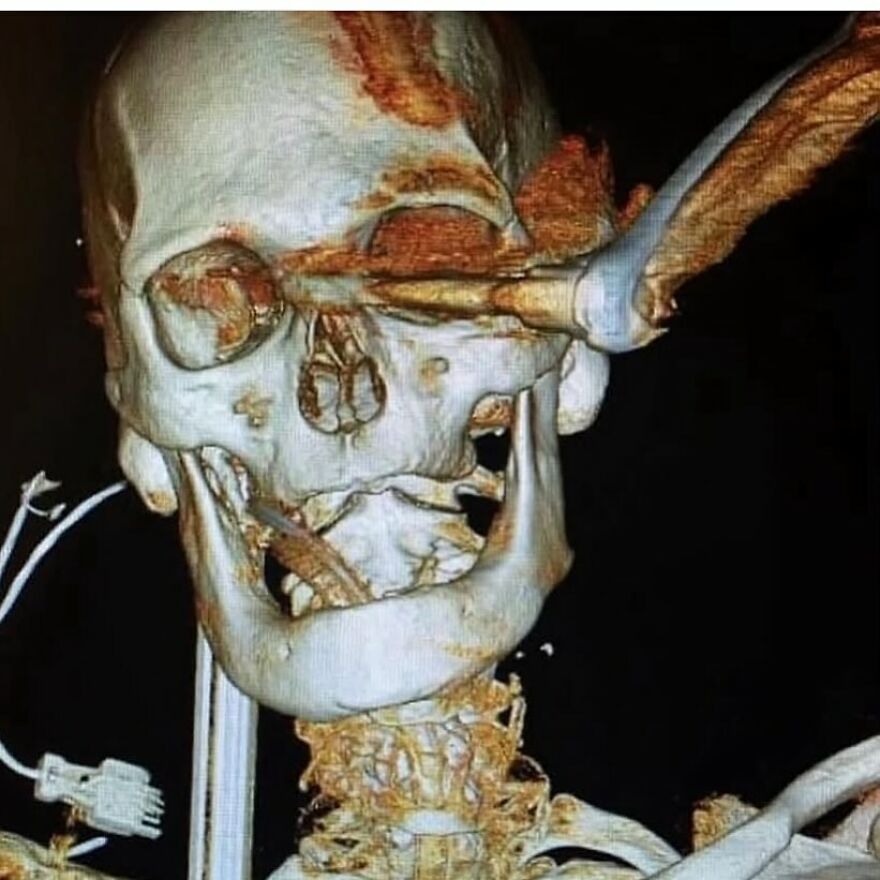

Skull of a person who had skeletal cancer